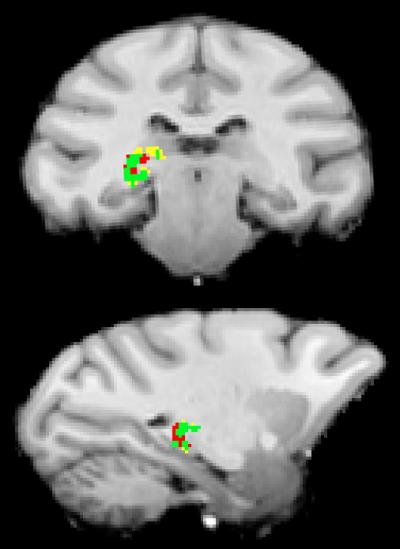

The researchers developed a new technique to trace direct communication between clusters of neurons in the visual cortex and the pulvinar. The team produced neural connection maps using magnetic resonance imaging (MRI), then placed electrodes along those identified communication paths to monitor brain signals of macaques. The researchers trained the monkeys to play a video game during which they used visual cues to find a specific shape surrounded by distracting information. As the macaques focused, Saalmann and his colleagues could see that the pulvinar controlled which parts of the visual cortex sent and received signals.

"To 'listen in' on a direct cell conversation, we developed a new approach of using electrodes to record groups of brain cells that were anatomically connected. We first mapped neural connections in the brain via diffusion tensor imaging, which uses an MRI scanner to measure the movement of water along neural connections. We then used these images to implant electrodes at the endpoints of the neural connections shared by the pulvinar and the visual cortex.